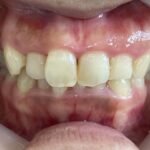

20代女性「ガタガタの歯と深い噛み合わせが気になる」取り外し式のマウスピース型矯正装置「インビザラインフル」で歯並びを整え、正しい位置で噛めるようにした症例

拝見したところ、歯並びの幅が狭くスペースが不足していることにより、歯がガタガタと並んでいる「叢生(そうせい)」でした。

特に上の前歯(右上中切歯/1番)は、ねじれて前方に突き出しており、見た目が気になりました。

また、上の歯が下の歯に覆い被さっている深い噛み合わせの「過蓋咬合(かがいこうごう)」も認められ、あごの関節に負担がかかりやすくなっていました。